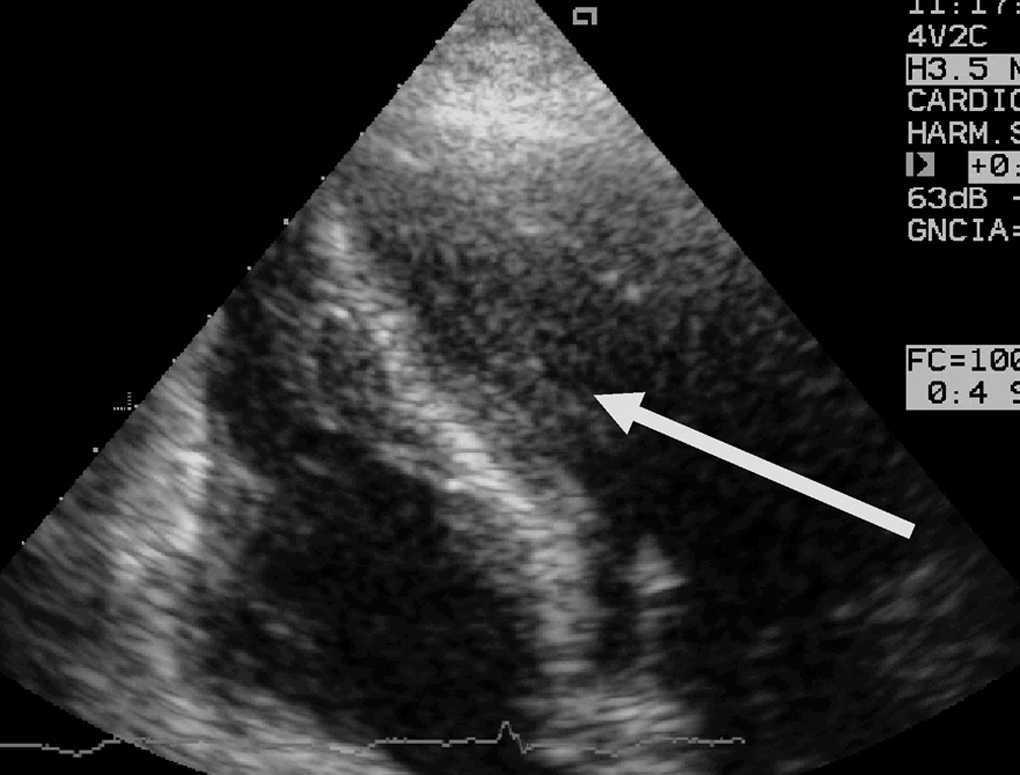

Aparte de la heterogeneidad de las distintas descripciones, de todos los estudios publicados se desprende que en presencia de patología neurológica grave se puede producir una disfunción miocárdica con una incidencia desconocida, pero que podría estar en torno al 9%, que mejora habitualmente en la primera semana, y es reversible en la mayoría de los supervivientes entre el primer y el sexto mes. Aunque la causa del fallecimiento es dependiente de la propia patología cerebral, dicha disfunción miocárdica reversible puede contribuir a la mortalidad, o al menos incrementar la morbilidad al poder cursar con complicaciones tales como arritmias potencialmente letales15,29, hipotensión arterial, edema pulmonar15,29, hipoxemia13-21, que podrían potenciar las lesiones cerebrales secundarias, así como formación de trombos intracavitarios en el ventrículo izquierdo12,14,15,18 que podrían provocar embolias15 (fig. 2). Por otra parte, esta disfunción miocárdica puede ser una causa directa del edema neurogénico o al menos contribuir a su desarrollo, ya sea por la propia disfunción ventricular sistólica o por otras complicaciones asociadas, tales como una insuficiencia mitral grave (figs. 3 y 4).

Figura 3. Ecocardiografía transtorácica, plano apical 2 cámaras, donde se puede observar un aneurisma septo e inferoapical de un paciente con hemorragia intracraneal complicada con edema neurogénico. La coronariografía realizada fue normal.